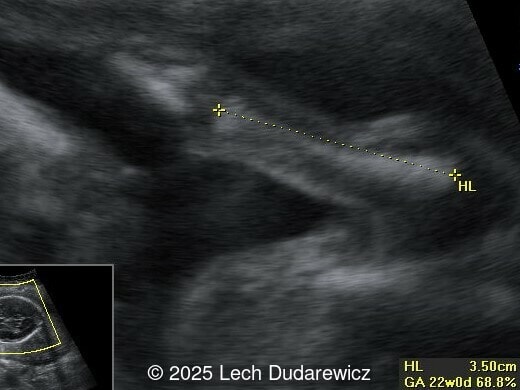

Ultrasound revealed a single live fetus with 46,XY karyotype. Biometric measurements demonstrated discrepancies with the femur and tibia length lagging significantly at 19 weeks and notable shortening and bowing of the femur, tibia, and fibula. The findings were consistent with skeletal dysplasia.

Prenatal ultrasound is a crucial tool for early diagnosis, enabling appropriate counseling and perinatal management of campomelic dysplasia. Key skeletal abnormalities include significant shortening and bowing of long bones, particularly the femur and tibia. In a study by Mansour et al, the lower extremities are primarily involved with minimal bowing of the humerus, ulna, and radius. Bowing often presents with associated angulation, giving rise to the term "campomelia," meaning bent limbs in Greek. Hypoplastic iliac bones and scapulae are hallmark features, while rib anomalies such as deformities or reduced number, typically 11 pairs, may also be observed. Additionally, the chest may be narrow and bell-shaped. Cervical spine abnormalities, including excessive lordosis or kyphosis, are often present and may contribute to postnatal respiratory complications. These findings are important for risk stratification and delivery planning.

Distinguishing between campomelic dysplasia and other skeletal dysplasias, such as thanatophoric dysplasia, osteogenesis imperfecta, hypophosphatasia or achondrogenesis, is critical. Differentiating angular bending of long bones, particularly the femur and tibia, in campomelic dysplasia from fractures in osteogenesis imperfecta type II is based on the following: Fractures in osteogenesis imperfecta type II are irregular, asymmetrical, and affect not only the long bones (especially in the lower limbs) but also the ribs and clavicles. In campomelic dysplasia, the bends are symmetric, have a regular shape, are usually located in the middle of the long bone shaft, and primarily involve the femur and tibia, with other bones being affected to a lesser extent. This may resemble a ‘French telephone receiver.’ Other key distinguishing features of campomelic dysplasia include the specific combination of bowed long bones, hypoplastic scapulae and iliac bones, and associated craniofacial and soft tissue findings. Molecular genetic testing for SOX9 mutations confirms the diagnosis. In contrast, thanatophoric dysplasia is characterized by macrocephaly and severe proportionate shortening of the limbs. Osteogenesis imperfecta Type II and hypophosphatasia both demonstrate congenital osteopenia due to a defect in the mineralization of bone structure.